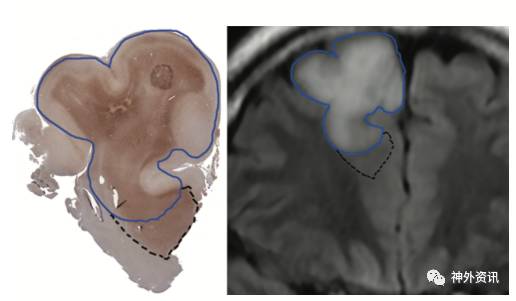

图3. 病例1患者影像学显示的肿瘤边界外肿瘤细胞富集区域。左图:在IDH1免疫组化染色图中实线为影像学显示的肿瘤边界,虚线为肿瘤边界外的肿瘤细胞富集区。右图:MRI冠状位T2-FLAIR影像图,实线为肿瘤边界,虚线为边界外的肿瘤细胞富集区。